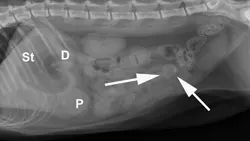

Abdominal radiography: Left/right lateral and VD views.

Radiographic Findings: The stomach (St) and duodenum (D) are severely distended with fluid and gas, suggesting intestinal obstruction or possibly pancreatitis with secondary ileus.

There is a 1.5-cm rounded opaque structure (arrows) in the caudal abdomen, to the left of the descending colon on the VD view. It is partially obscured by feces in the colon (C) on the left lateral view. The remaining organs and serosal detail appear normal.

Comments: We often perform left and right lateral radiographic views of the abdomen in cases of suspected GI foreign bodies and obstructions since the fluid and gas disperse into different portions of the GI tract. For example, any gas in the stomach rises to the pylorus (P) in left lateral recumbency and may outline a foreign body anchored to this region; this is particularly useful in suspected linear foreign bodies, which typically anchor to the tongue or pylorus and subsequently plicate varying degrees of small intestine.